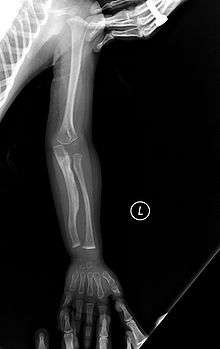

Type V

Having the same clinical features as Type IV, it is distinguished histologically by "mesh-like" bone appearance. Further characterized by the "V triad" consisting of a) radio-opaque band adjacent to growth plates, b) hypertrophic calluses at fracture sites, and c) calcification of the radio-ulnar interosseous membrane.[12]

OI Type V leads to calcification of the membrane between the two forearm bones, making it difficult to turn the wrist. Another symptom is abnormally large amounts of repair tissue (hyperplasic callus) at the site of fractures. Other features of this condition include radial head dislocation, long bone bowing, and mixed hearing loss.